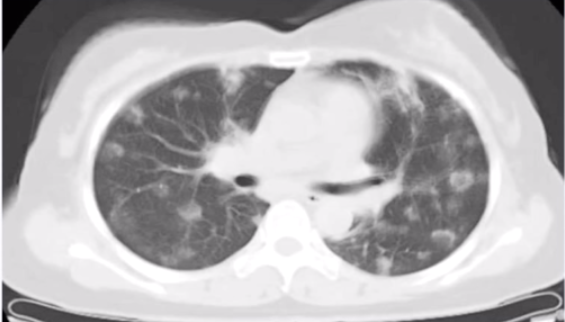

反晕征伴小结节,指示肺结节病

图源:张嵩《诊断必备:肺部 CT 的诊断技巧及误区》

结节病中的反晕征是许多小结节组成的。在反晕征和微小结节同时存在时,需要考虑结节病的可能。本病例即结节病,CT 表现为反晕征、多发结节,在激素治疗后好转。